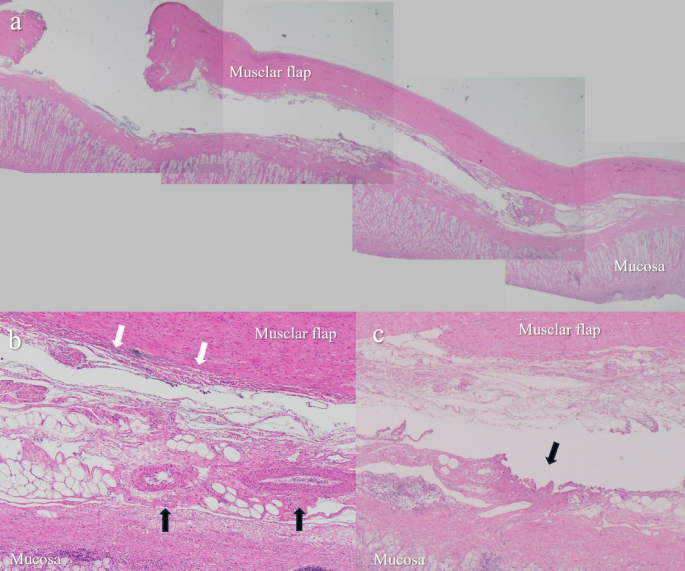

Microscopic dissection line

After formalin fixation of the stomachs, 27 HE-stained sections excised from 9 flaps in each group were examined microscopically (Fig. 3a). In both groups, muscular flaps were dissected not between the submucosal layer and the muscular layer but within the submucosal layer (Fig. 3b). Dense connective tissue, including blood and lymphatic vessels, was preserved on the mucosal side. The dissection line was observed in the outer layer of this dense connective tissues and did not differ between the two groups.

Microscopic images of porcine stomach wall after dissection. (a) The muscular flap was dissected from the submucosal layer using the SFC method. The flap length is approximately 12.5 mm. (b) A small amount of submucosal tissue remained on the muscular layer after dissection with the SFC method (white arrows), while blood and lymphatic vessels in the submucosal layer were preserved on the mucosal side (black arrows). (c) Thermal damage on the mucosal side surface after dissection without the SFC method (black arrow).

Thermal damage

The total length of thermal damage on the flap side was significantly shorter in the SFC group (median: 0.76 mm) compared to the control group (median: 2.82 mm; p < 0.001). Similarly, thermal damage on the mucosal side was significantly reduced in the SFC group (median: 0.7 mm) compared to the control group (median: 3.79 mm; p < 0.001) (Table 2; Fig. 3c).